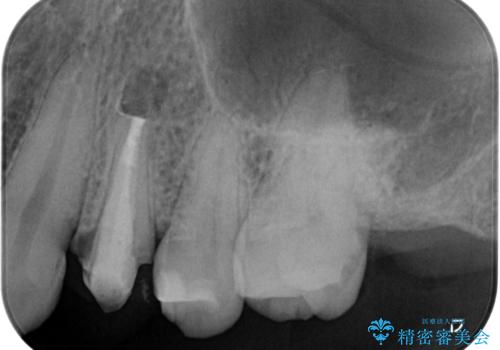

再根管治療を優先した理由としては、破折診断と、当時の治療においてラバーダムや顕微鏡を使用してないとの話があったためです。

結果、根管内にはイスムスにデブリが多く見られたものの破折線は確認できませんでした。再根管治療後、症状の経過を3ヶ月ほど確認しましたが打診、違和感が消失しておらず、外科的歯内療法を行うこととなりました。